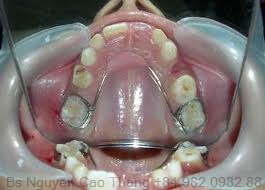

- Hàm giả cố định: Răng giả cố định ở trẻ em là các loại răng giả gắn cố định vào các răng còn lại, có thể là chụp răng hay cầu răng hoặc một biến thể của răng giả tháo lắp.

- Chụp có sẵn dùng cho trẻ em: Là các loại chụp được sản xuất sẵn theo nhiều kích thước khác nhau cho từng loại răng khác nhau.

Chụp có sẵn này có thể được làm bằng thép không gỉ hoặc bằng nhựa carboxylate. Ưu điểm của các loại chụp thép có sẵn là: thao tác nhanh, kết quả tốt, lâu dài hơn so với các phục hồi thông thường, mài răng ít, có khả năng bảo tồn tủy răng cao, giá rẻ, tránh được sâu răng tái phát, giữ được chiều cao khớp cắn, đặc biệt trong các trường hợp bất thường cấu trúc gây mòn răng nhanh, giữ được chiều dài cung răng.

Chỉ định của chụp thép có sẵn: răng sau khi chữa tủy hoặc lấy tủy buồng, răng bị sâu nhiều mặt, răng bị vỡ lớn, răng chấn thương, làm trụ cho hàm giữ khoảng cố định hay tháo lắp hoặc đeo hàm giả, bất thường cấu trúc răng (sinh men bất toàn, sinh ngà bất toàn), dự phòng đa sâu răng và sâu răng tái phát ở các trẻ em có nguy cơ sâu răng cao hoặc trẻ khuyết tật khả năng vệ sinh răng miệng kém. Đối với các răng sữa được lấy tủy buồng, việc phục hồi thân răng bằng các loại chụp là hết sức cần thiết để tránh sự thâm nhiễm nước bọt và/hoặc tránh vỡ thân răng.